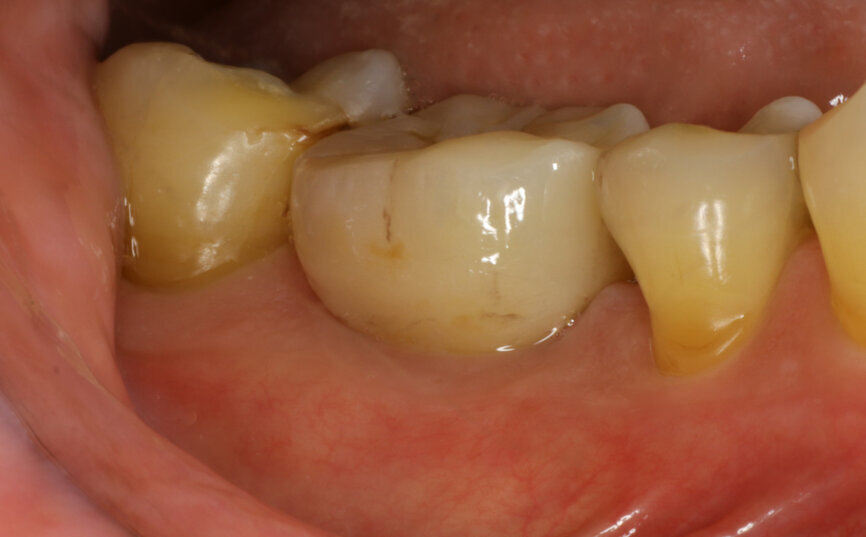

Initial situation

A 68-year-old male patient, a non-smoker, presented with controlled Type 2 diabetes. He had undergone previous dental implant treatments with positive results in the past. The patient presented to the office with tooth #36 in a non-restorable condition with indication for extraction. He requested a dental implant as the treatment choice.

Fig. 1: Intra-oral occlusal view.